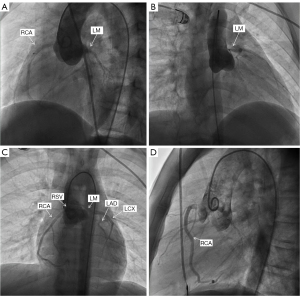

Coronary angiography (external hospital examination, 21 days after the onset of the disease, Figure 6) showed that the LCA appeared to open at the RCS with a high opening, and the initial part of the left coronary stenosis showed a beak-like change.